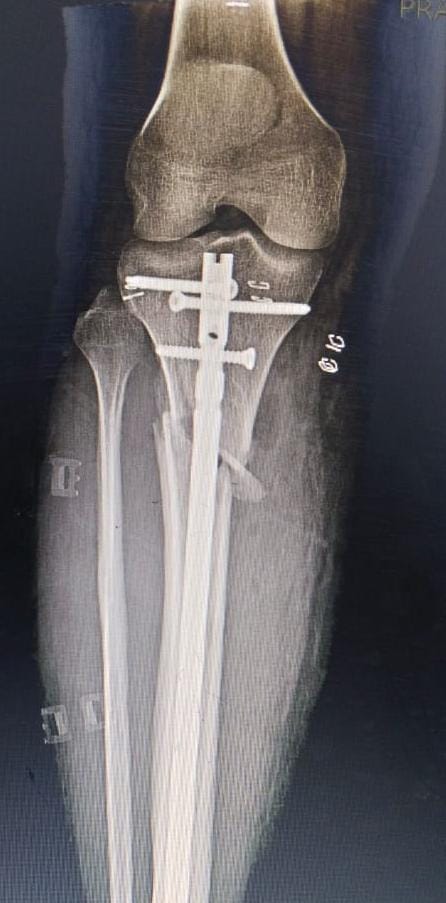

Fracture surgery is a procedure to repair broken bones, ensuring proper alignment and stability for optimal healing.